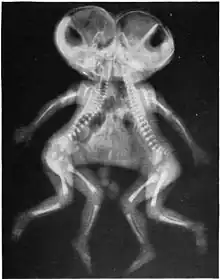

| X-ray of conjoined twins, Cephalothoracopagus. | |

- Cephalothoracopagus: Bodies fused at the head and thorax, with two faces facing in opposite directions, or sometimes with a single face and an enlarged skull.[13][15]